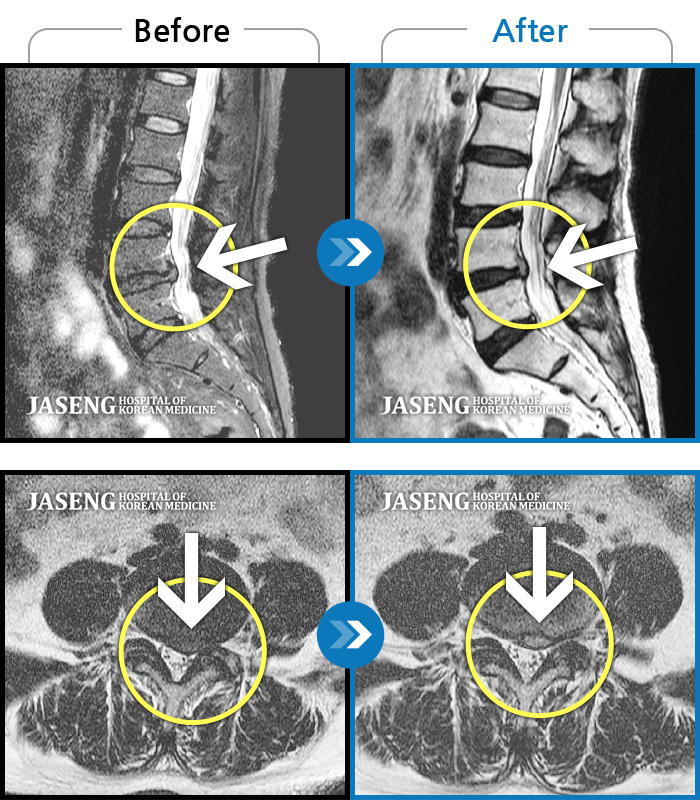

허리디스크

인천 · 강아현 원장

좌측 허리 통증 및 골반 통증이 심하여 걷는 것도 힘든 상태로 내원하셨습니다.

촬영시기

2024.05.08 ~ 2025.11.12

2025.11.14

조회수 128